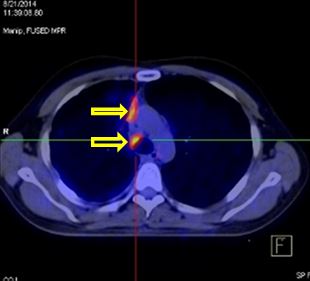

Hình ảnh PET/CT sau 8 chu kỳ Cisplatin-Pemetrexed - Bevacizumab

Nhiều nốt mờ rải rác phổi phải, màng phổi, max SUV = 4,7. Hạch cạnh khí quản 1,5 cm, max SUV = 6,4 (đầu mũi tên)